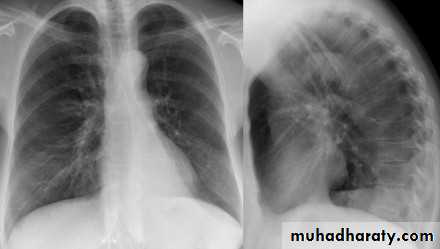

44.A.RT middle lobe consolidation

B.RT middle lobe collapse